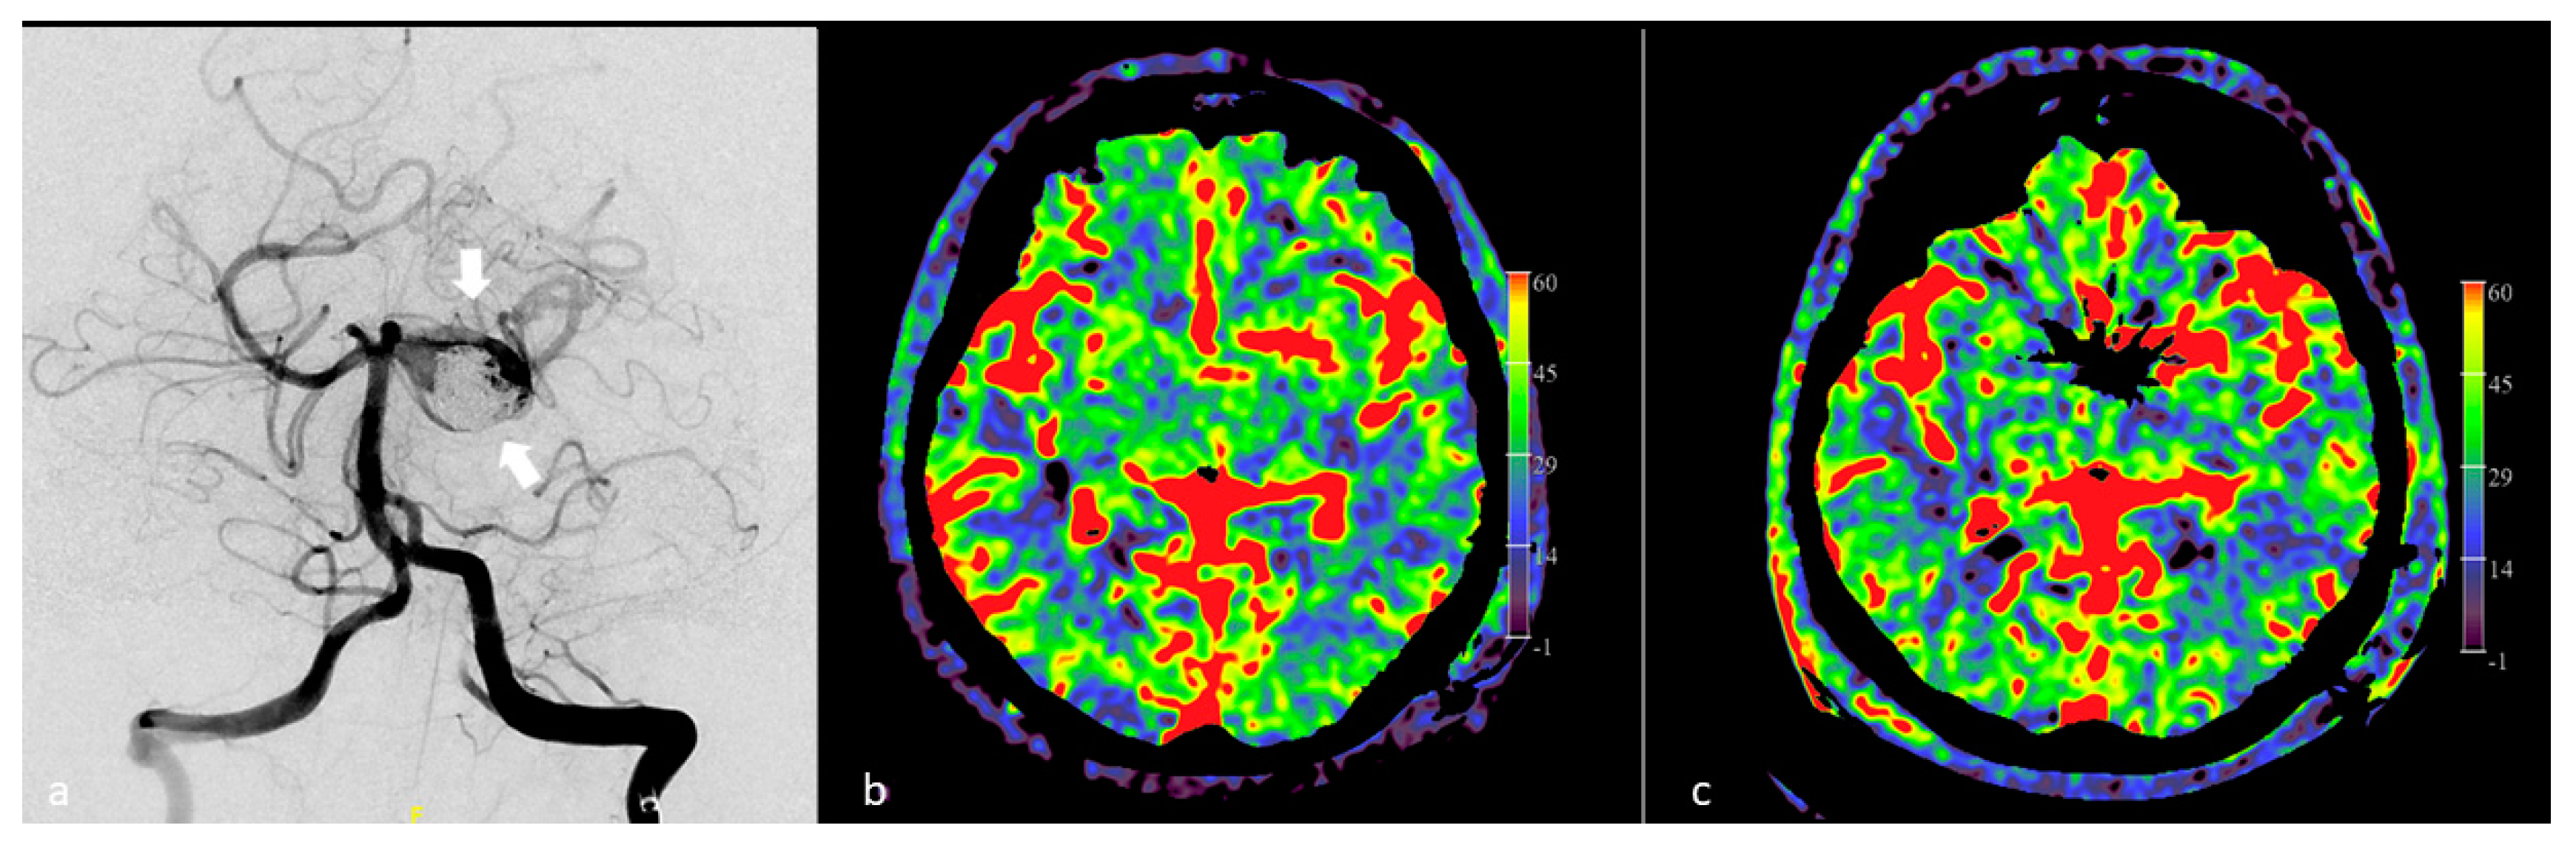

Thus, real-time FD CT perfusion imaging in the angiography suite can be of great value, not only for documenting vasospasm and perfusion abnormalities, but also as a diagnostic tool for assessment of intra-arterial treatment response. Besides semiquantitative measurement of angiographic parameters, such as vessel diameters, amount of angiographic staining of the affected brain areas and measurement of color-coded 2D parenchymal perfusion parameters, e.g., contrast bolus arrival time, TTP and MTT, it is possible to compare regional PBV values before, during and after intra-arterial treatment. In this way, proper treatment endpoints of endovascular vasospasm therapy can be established, reducing the risk of procedural complications. In Figure 9, the applicability of FD CT PBV imaging in a patient with post-subarachnoid hemorrhage vasospasm is illustrated.

Figure 9.

FD CT PBV imaging in a 44-year-old patient after subarachnoid hemorrhage with symptomatic vasospasm. (a) DSA in AP view demonstrates severe vasospasm at the level of the left distal internal carotid artery, proximal anterior and middle cerebral arteries (white arrows). (b) FD CT PBV mapping with PBV measurements before EVT, displaying lower PBV values at the left hemisphere, compared to the right hemisphere. (c) DSA image post dilatation shows favorable angiographic response to PTA. (d) Post PTA FD CT PBV measurements show improvement of the PBV value at the left hemisphere compared to the right hemisphere.